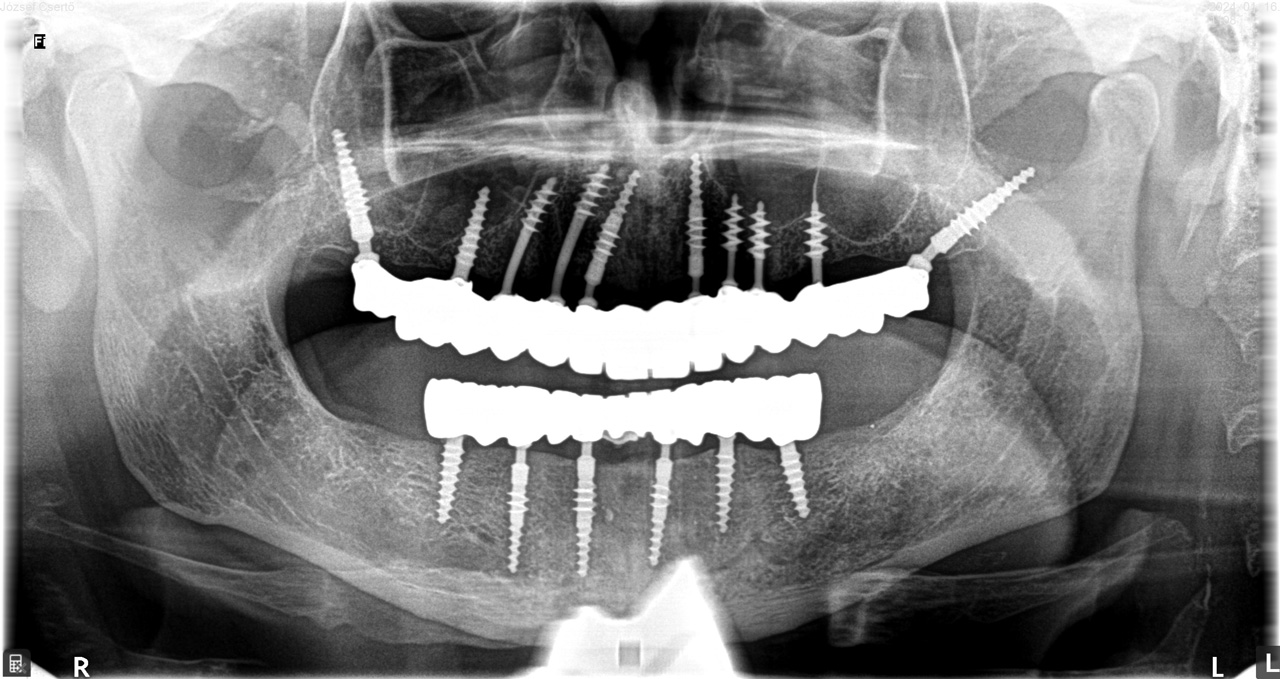

Teljes fogatlanság helyreállítása 2 nap alatt

Teljes fogatlanság helyreállítása 2 nap alatt azonnal terhelhető svájci IHDE implantátumokkal és PMMA műanyag hidakkal. Intraorális szkennerrel vettünk lenyomatot az implantáció után, és erre a digitális mintára készítette el a fogtechnika a hidak digitális tervezését, majd faragta ki műanyagból. Ezt a gyors munkát az azonnal terhelhető implantátumok és a digitális lenyomat, tervezés segítségével tudtuk megcsinálni mindössze 2 nap alatt. Dr. Kelemen Péter és a Symbion Fogtechnika munkája.